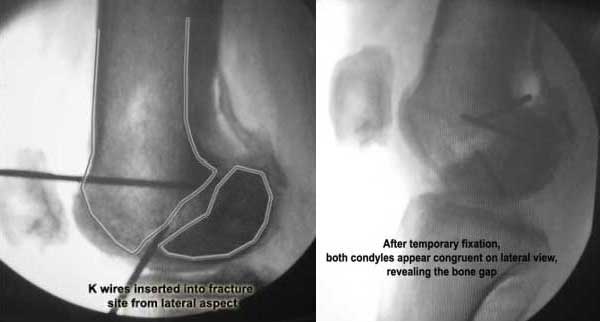

I opened it up from the lateral aspect.

Freed up the non-union site with minimal disturbance to the posterior and lateral soft tissue attachments on the lateral condyle fragment.

Applied a distractor between femoral shaft and tibia, to create a space on the lateral aspect.

This brought the lateral condylar fragment into a position that seemed to be reasonably well aligned, but showed up a bone gap.

This was fixed temporarily, bone grafted with tricortical struts, and fixed by two cancellous screws. The fragment was not large enough to afford any fixation to a plate or such implant, and the screws held it compressed well to the rest of the distal femur.

Pictures attached.